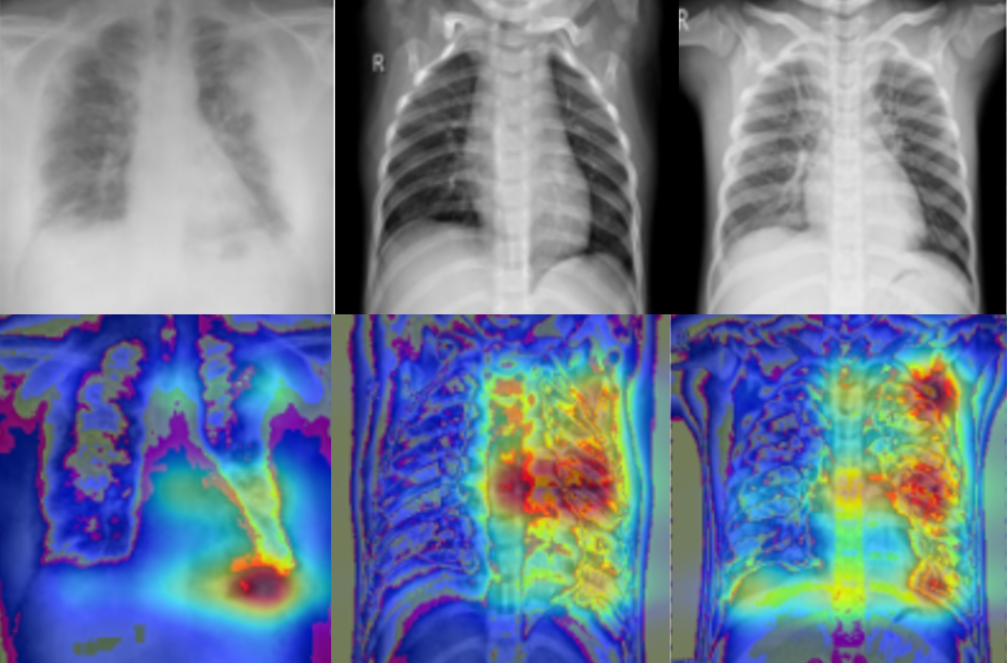

Developement of an algorithm to detect toracic x-ray images with covid induced pneumonia from healthy subject and patients with non-covid related pneumonia.